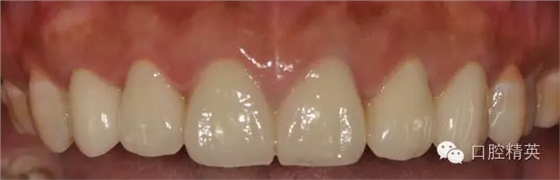

原金屬烤瓷冠

原金屬烤瓷牙咬頜觀